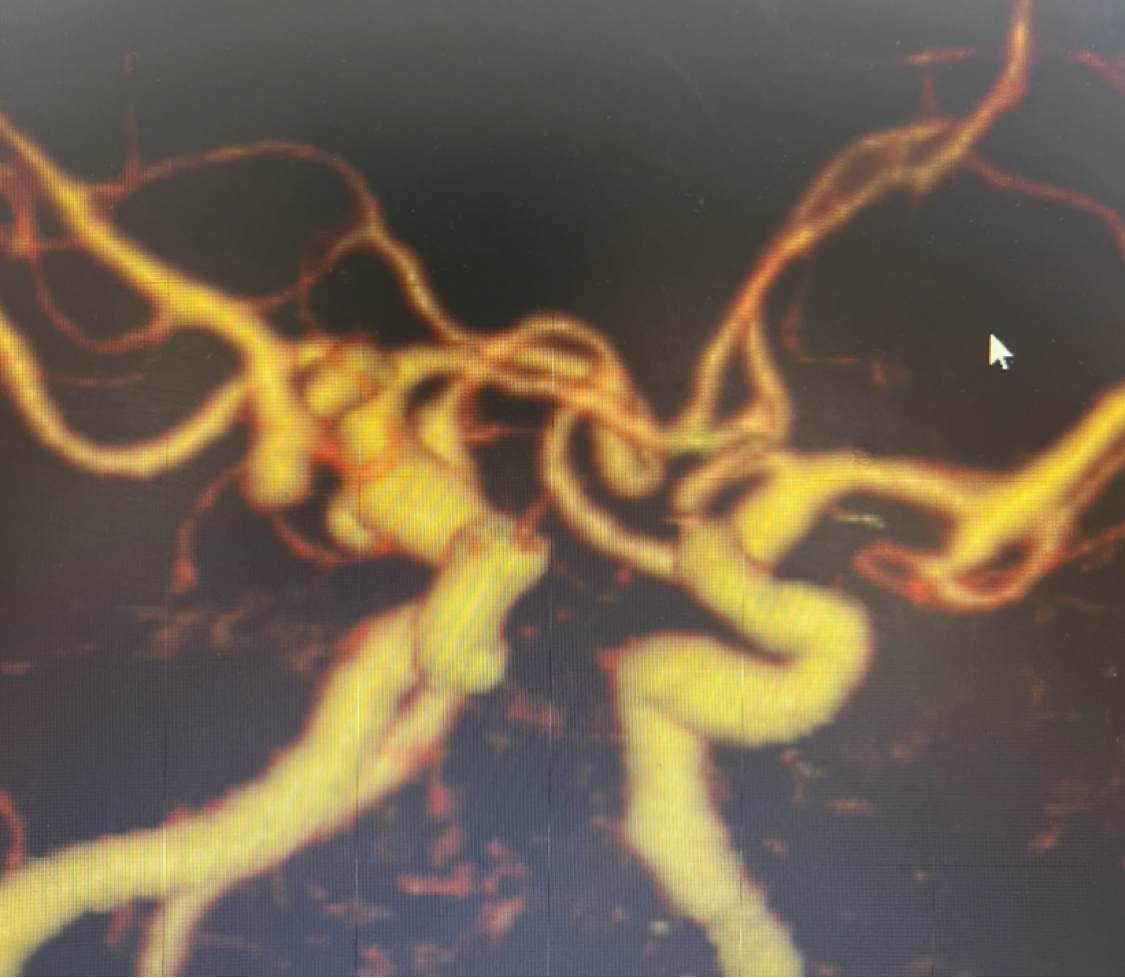

DSA:双侧大脑前动脉A1段存在,右侧A1段与前交通动脉结合处囊状凸起,最大径约2.8m m

6F中间导管超选至左侧颈内动脉岩段,内套V18超硬导丝提高支撑力,退出微导丝。路图下微导丝辅助Prowler Select Plus微导管超选至右侧A2远端,备释放支架。上高中间导管至C4段。HEADWAY微导管塑形后微导丝辅助下超选至动脉瘤内。选择APB2mm/6cm HX-ES弹簧圈填入动脉瘤内稳定成篮。即刻造影提示动脉瘤瘤体、瘤颈未见明显显影,载瘤动脉通畅。考虑患者急性期,遂结束,拟3个月后复查DSA,根据复查情况考虑是否需要后期贴敷支架治疗。